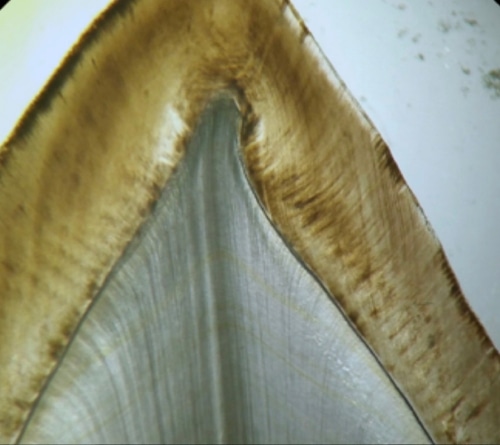

Y, por ultimo, esta la zona granulosa de Tomes. Que se observa como una franja oscura unida hacia el cemento del diente.